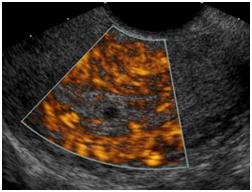

Pelvic Ultrasound

Your doctor has ordered an ultrasound of your pelvis. Ultrasound is a safe and painless procedure that uses sound waves to assess the structure of your internal body organs. The scan can help diagnose such medical conditions as pelvic masses in the uterus and ovaries.

- Sound waves will bounce off certain organs and tissue in your body. This creates "echoes." The echoes are reflected back to the transducer, which converts them to electronic signals. A computer then processes the signals into pictures for radiologist evaluation.